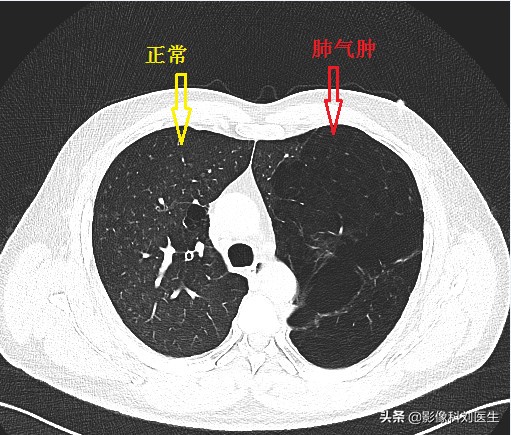

首先给大家看几张CT图像:

通过上面的图像,相信大家有了一个大概的印象。肺气肿主要征象即为正常肺组织内出现无囊壁的低密度区。

首先,我们来看小叶中央型肺气肿。它是一种与吸烟相关的肺部疾病,主要累及肺上叶、呼吸性细支气管破坏融合,肺泡导管肺泡囊正常,在CT上主要表现为散在分布的小圆形、无壁的低密度区,直径一般约2-10mm,位于肺小叶中央,仍可见小叶核心内的动脉。